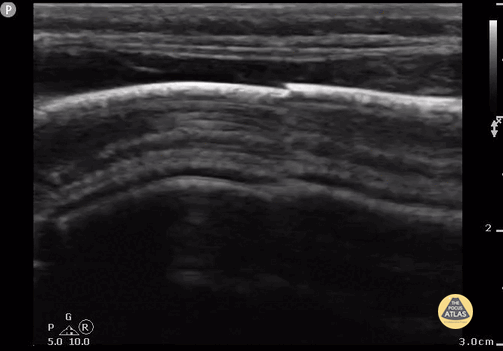

9 month old with non-displaced parietal skull fracture. Note the diagonal jagged appearance of bony overlap. Contributor: Antonio Riera, MD